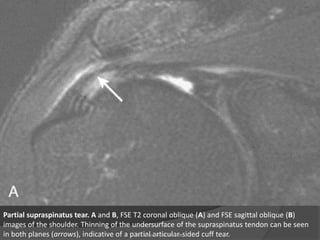

Partial supraspinatus tear. A and B, FSE T2 coronal oblique (A) and FSE sagittal oblique (B)

images of the shoulder. Thinning of the undersurface of the supraspinatus tendon can be seen

in both planes (arrows), indicative of a partial articular-sided cuff tear.

• 33.

Partial supraspinatus tear.A and B, FSE T2 coronal oblique (A) and FSE sagittal oblique (B) images of the shoulder. Thinning of the undersurface of the supraspinatus tendon can be seen in both planes (arrows), indicative of a partial articular-sided cuff tear. Dr. Emanuel R. Dantas